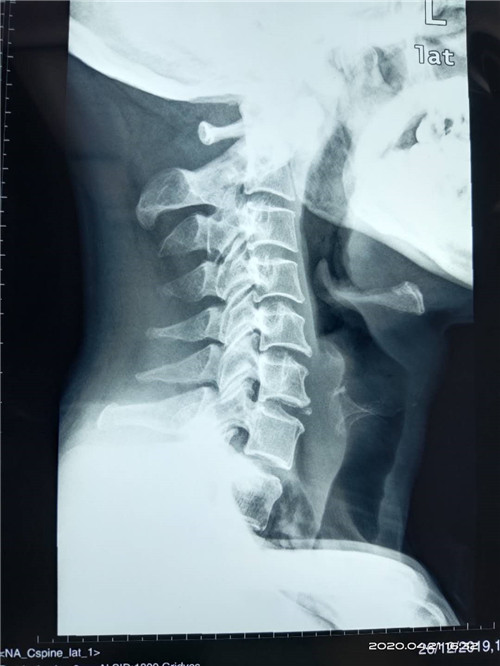

近日,昆明市延安医院呈贡医院(呈贡区人民医院、呈贡区中医医院)外一科为一位寰枢关节脱位患者成功实施了后入路颈1、2复位椎弓根螺钉内固定手术,患者术前诊断为:“寰枢关节脱位”。曾到过省内多家大医院就诊,因害怕手术风险,未敢做手术,后慕名前来我院,外一科主任杨旭民主任医师仔细查看患者及相关资料后收住院,并与患者及家属耐心讲解病情及手术方法、手术风险后,患者同意在我院手术,经过术前准备后于4月21日外一科在杨旭民主任带领下为患者成功实施了后入路颈1、2复位椎弓根螺钉内固定手术。术后患者寰枢关节脱位完全复位,固定满意。于4月22日由ICU安全转回普通病房。

术前图片如下:

小提示:寰枢关节脱位是指颈椎第一节(寰椎)第二节(枢椎)之间的关节失去正常的对合关系。主要表现为头昏、头痛、颈部疼痛、四肢无力、走路不稳、呼吸障碍等。危害:可累及四肢、呼吸系统、神经系统甚至危及生命。治疗的方法主要还是手术。

上颈段手术是骨科风险较高的手术,要求术者具有丰富的临床经验及高超的手术技巧,同时需要与医院各科室(临床、麻醉、检验、放射、重症监护室)紧密合作才能完成,我院成功完成了该手术标志着我院骨科技术水平上了一个台阶,同时也表明患者对我院的医疗水平得到了患者的高度信任。